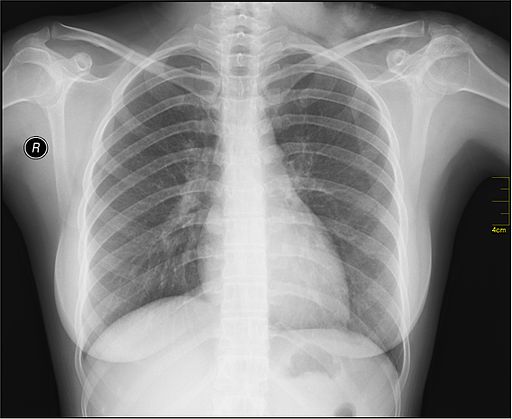

X光的發現不僅為科學發展開啟新紀元,也因為它具有絕佳的穿透性,而延伸開發成各種非破壞性的檢測儀器,廣泛地應用在醫療、科技、生活與美學等領域之中。在這個單元我們要討論的是穿透式X光影像(Transmitting X-ray),也就是醫院最常見的一般X射線攝影(X-radiography),用來查看骨骼是否受傷斷裂、內臟器官是否有異常的組織生長。或者是搭飛機前的飛安檢查,安檢人員也會利用X光快速查看旅客行李是否有違禁品。也就是說,我們利用穿透式X光獲得超人的「透視」能力,穿透人體或物品的表層來觀察內部結構。

使用X光查看人體內部

© Nevit Dilmen, CC BY-SA 3.0 <https://creativecommons.org/licenses/by-sa/3.0>, via Wikimedia Commons

拍攝X光影像有點類似用手電筒玩手影遊戲。手電筒的光穿不透手,所以可以在牆上投影出實心的手影,但若換成透明的玻璃杯,則只會有淺淺的陰影。由於不同物質對X光有不同的吸收或穿透率,當使用X光照射時,會在被測物背後的成像板上投影出深淺不一的對比影像,便可依此將不同成份的物質區分出來。但是什麼因素決定了X光對物質的穿透程度呢?

我們知道萬物皆由原子組成,原子中心有原子核,原子核周遭環繞電子,這些電子對X光而言就好像路障一樣,X光行徑時若撞到電子便會損失能量。當X光通過原子序較高的物質(含有較多電子)時,因為路障的密度或數量增加了,就比較容易被阻擋而降低穿透率。同理,增加物質的厚度也會有一樣的效果。

拍攝X光影像時,X光射源在物品之前,射源發出的X光會穿透物品,並且投影在物品背後的成像板上。物品越貼近成像版,影像輪廓越清晰。透過改變射源的電壓、電流與曝光時間,可調整X光的穿透力、影像清晰度以及影像明暗。不過由於X光影像是平面的投影成像,立體或多層次物件的重疊結構會同時疊加在一起,這也是為什麼醫院會要求我們在拍攝X光時脫掉衣服、項鍊的原因。除了排除不必要的配件干擾以外,多換幾種角度拍攝也能讓我們對立體物件結構的理解更全面。